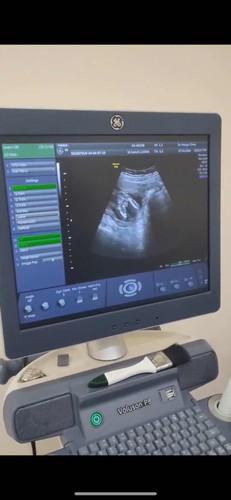

17w+1 แม่ๆช่วยเดาเพศหน่อยค่ะ

คุณบอกเพศหญิง 70% แต่น้องให้เห็นไม่ชัด แม่ก็คิดว่า ผญ แต่บางคนก็บอกว่า ผช ช่วยเดาหน่อยค่ะ